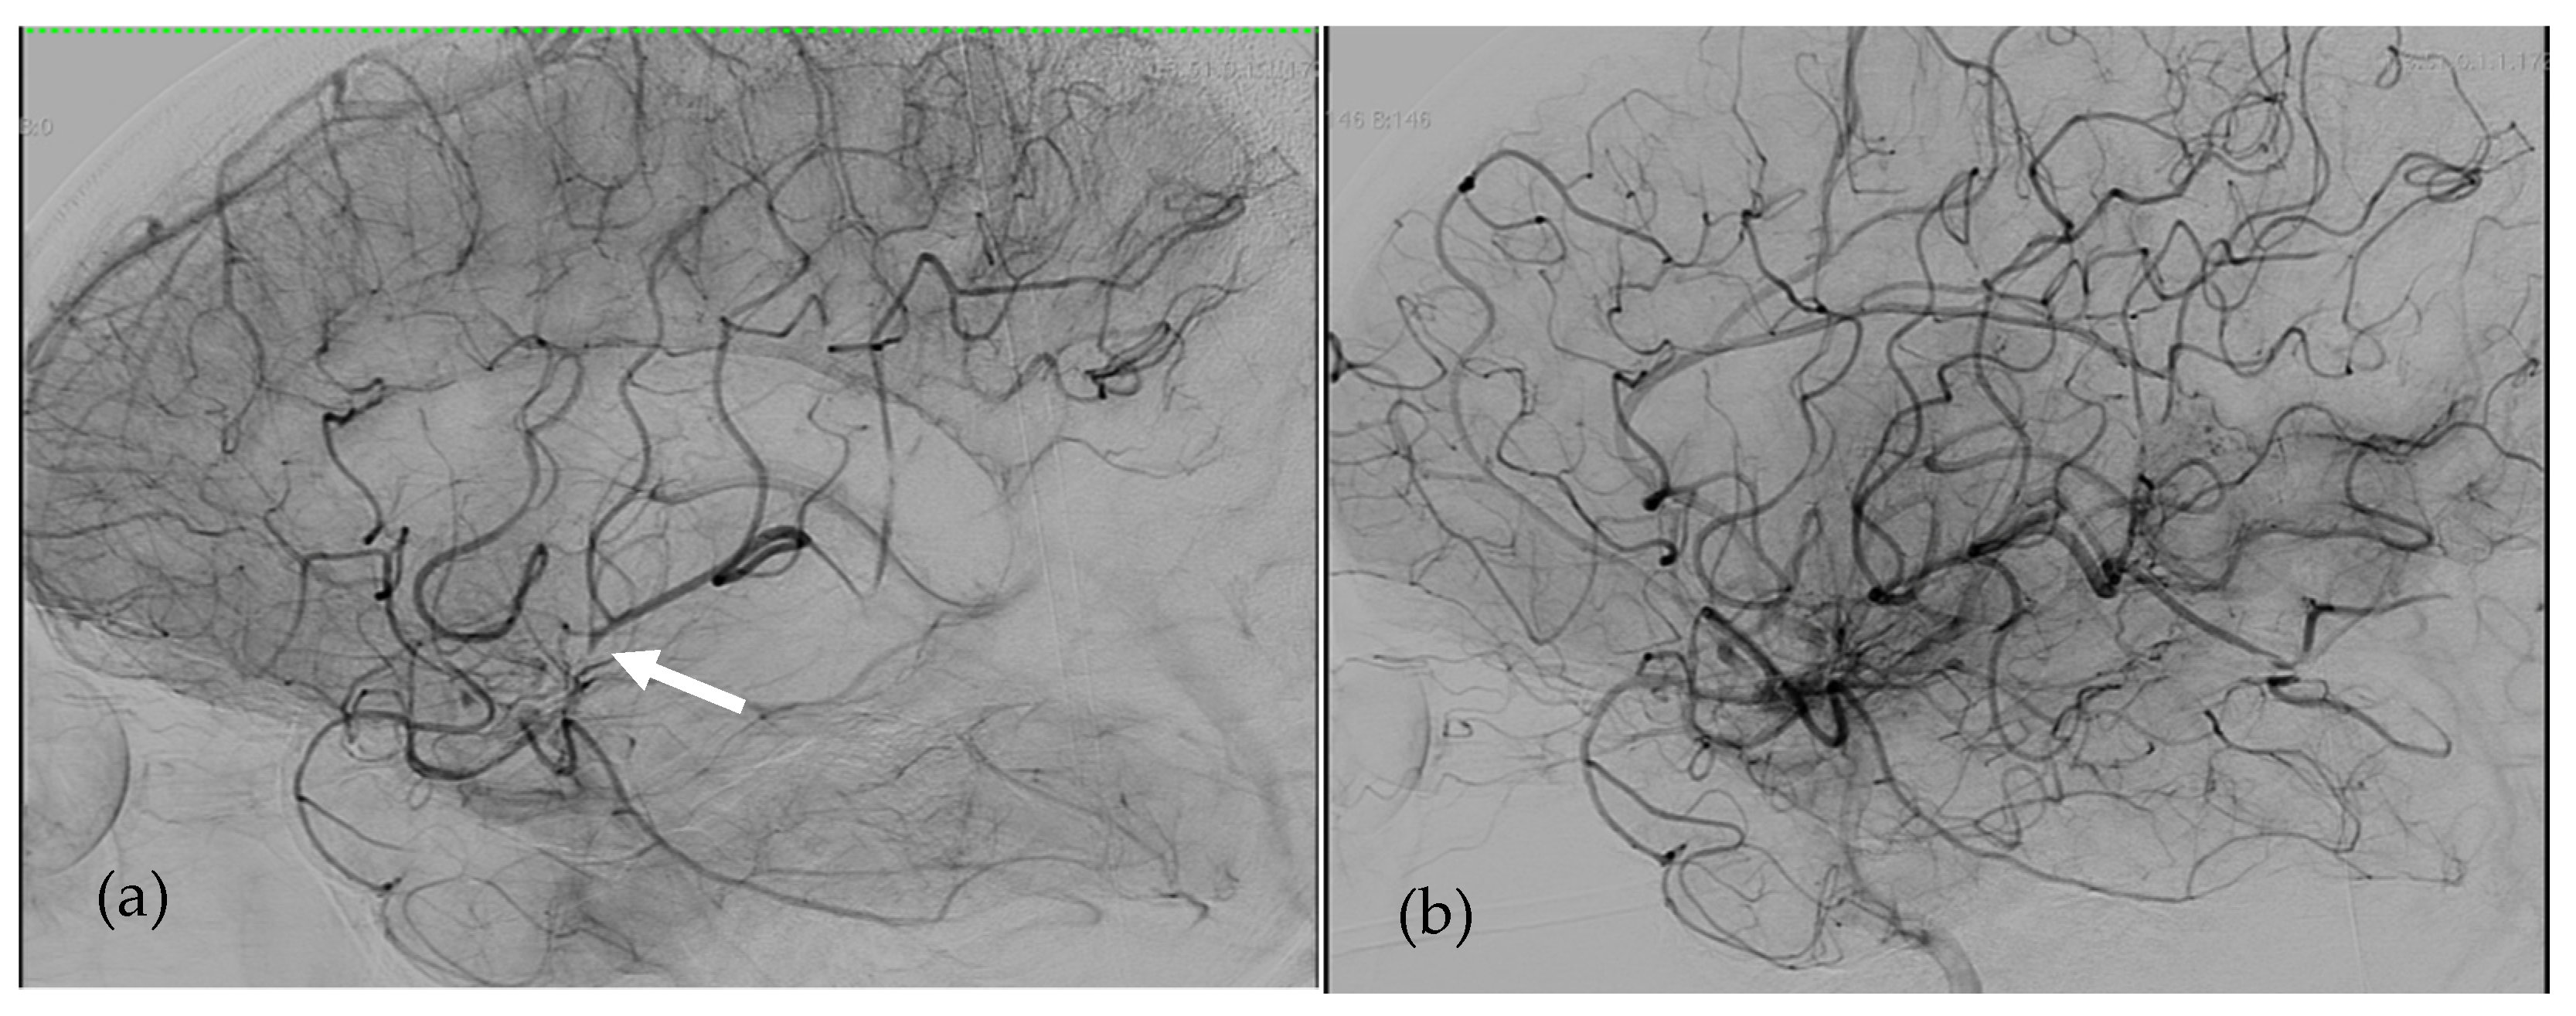

Figure 1. Angiographies of Left Internal Carotid Artery in patient 1. (a)Left Middle Cerebral Artery occlusion responsible for right hemiplegia just before revascularization (the white arrow shows the thrombus). (b) Early after endovascular revascularization by mechanical thrombectomy 100 min after the onset of the symptoms.

The first patient was a 44-year-old man, 1.90 m tall and weighing 94 kg (BMI 26 kg/m2), with end-stage ischemic heart failure, complicated by renal failure requiring extra-renal dialysis treatment. The patient was implanted with a 70cc SynCardia-TAH (body surface area: 2.22 m2). The anticoagulation protocol consisted of treatment with unfractionated heparin with an anti-Xa target activity of 0.20–0.40 IU/mL, associated with acetylsalicylic acid at 160 mg per day (acetylsalicylic acid was added after SynCardia implantation as soon as the hemorrhagic risk had been eliminated). He did not have any hemorrhagic complication but presented numerous thrombotic complications unrelated to heparin-induced thrombocytopenia or heparin resistance: deep vein thrombosis of the right internal jugular vein and vena cava, several small pulmonary embolisms responsible for a pulmonary infarction, right and left kidneys infarction, splenic infarction and several small ischemic strokes with no significant clinical translation (which, however, justified the administration of 160 mg of acetylsalicylic acid per day). The main thrombotic complication was the occurrence of an embolic ischemic stroke on the 57th day of assistance. This occurred due to an occlusion of the left middle cerebral artery responsible for right hemiplegia. In the 12 days prior to the stroke, his anti-Xa activity ranged from 0.3 to 0.7 IU/mL. At this time, relay by anti-vitamin K treatment was not initiated because unfractionated heparin was easier to manage in this patient’s context. The early in-hospital diagnosis of the neurological deficit allowed for rapid management by thrombo-aspiration with an aspiration catheter alone, performed 100 min after the onset of symptoms. This thrombectomy enabled immediate revascularization of the territory of the left middle cerebral artery. No hemorrhagic complications occurred following the thrombectomy despite the maintenance of anticoagulant and platelet anti-aggregation treatments without any modification in the immediate pre- and post-interventional period. Subsequently, the neurological deficit fully regressed and the patient had no adverse event. After this complication, therapeutic anticoagulation and platelet anti-aggregation with acetylsalicylic acid were continued according to the same protocol.